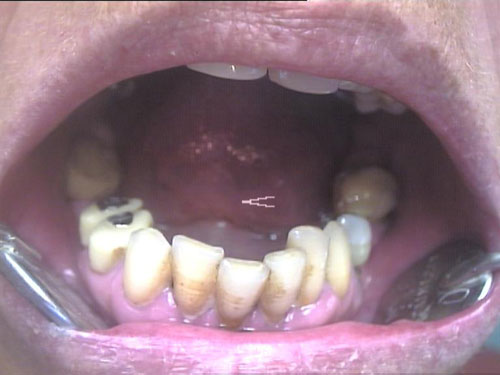

Zahn-Anomalien 1

Zahn-Anomalien 2

Zahn-Anomalien 3

Zahn-Anomalien 4

Zahn-Anomalien 5